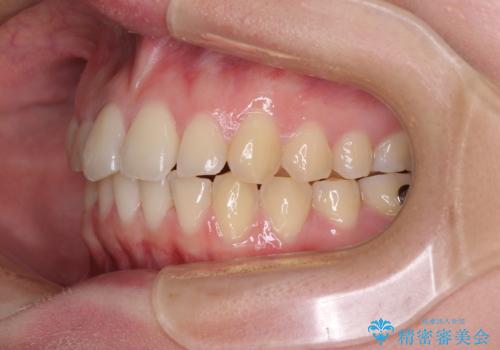

- 食いしばりが気になっていたとのことで来院された患者様です。

当初は睡眠時のマウスピースのみの製作をご希望でしたが、矯正治療の提案をしたところ、インビザラインにて矯正治療を行うこととなりました。

矯正治療中に食いしばりがより強くなることがあるため、半年に1回のペースでボツリヌストキシンによる咬合力緩和を並行して行うこととしました。

咬合力の緩和と食いしばりがちな咬み合わせが改善され、顎の負担が大幅に軽減されました。